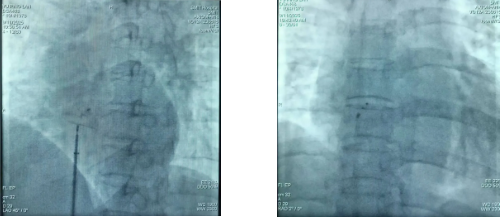

术后影像片